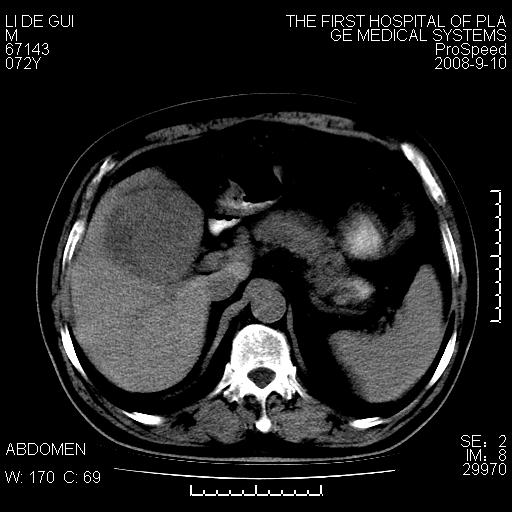

标题: CT17988:腹部肿块两年,肿块大小无变化,患者无不适,自我 [打印本页]

标题: CT17988:腹部肿块两年,肿块大小无变化,患者无不适,自我

胆囊占位性病变(黄色肉芽肿性胆囊炎?)。

考虑-----胆囊血肿机化或胆囊癌或腺肌增生症------增强

胆囊占位性病变,增强。

十二指肠的间质瘤